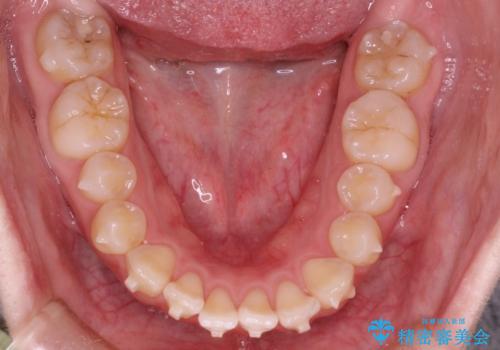

前歯にがたつきがあり、上下の歯が咬み合っていない状態でした。

歯列の横幅をひろげるのと、歯と歯の間をわずかに削ることにより、前歯のがたつきと、開咬を改善しました。